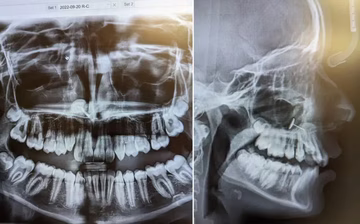

Neočekivana komplikacija Kćer odvela na rendgen zuba, a on je otkrio nešto što ondje nije smjelo biti Lifestyle | 17. kol. | 1